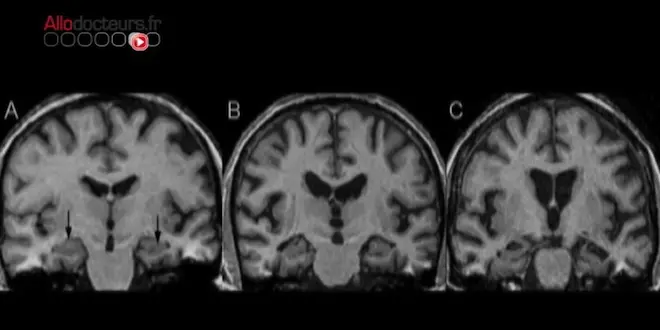

Le 21 septembre marque la journée mondiale de la maladie d'Alzheimer. Quelles sont ses causes ? Ses facteurs de risque ? Peut-on prévenir l'apparition de la maladie ? Sur quelles bases se fonde le diagnostic ? Existe-t-il des formes précoces de la maladie ?

Bien que la recherche ait enregistré des avancées substantielles durant la dernière décennie, de très nombreuses inconnues subsistent autour de la maladie d'Alzheimer.